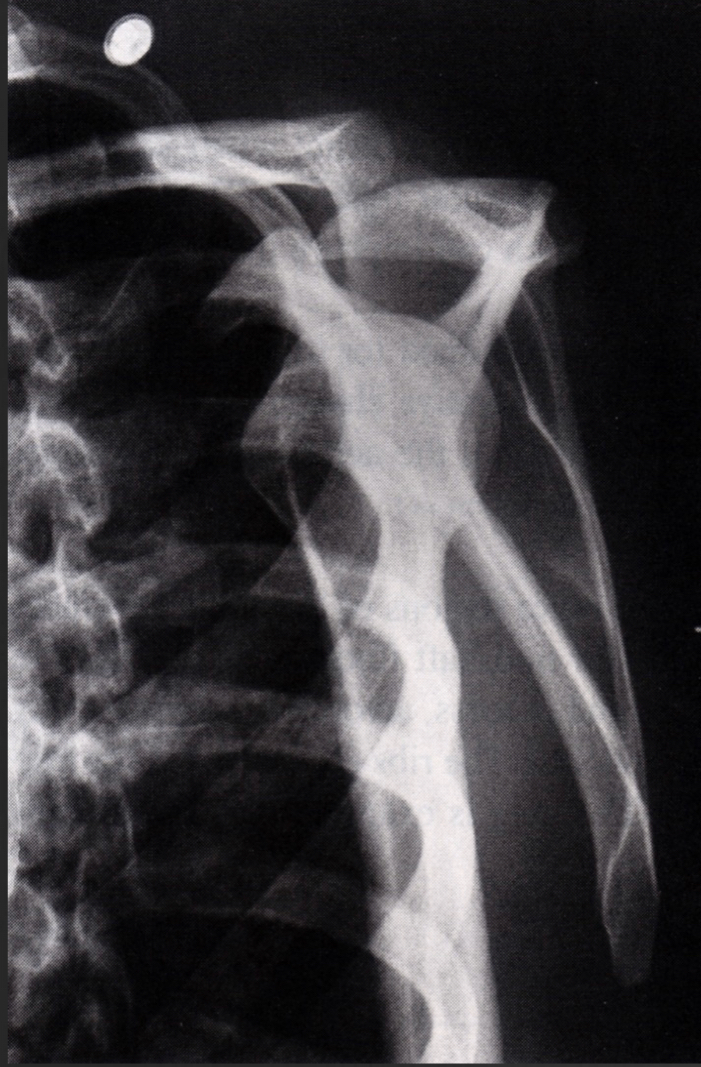

normal trans-scapular y view

normal Y

posterior dislocation lateral to the Y

anterior medial to the Y